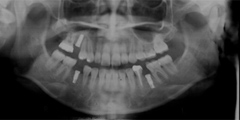

口内写真とパノラマレントゲンを撮影し、まずは顎の骨の状態まで詳しく確認しました。

写真(2)パノラマレントゲン写真

・歯がない期間が長く続いたため隣の歯が横に倒れてしまい、歯と歯との間に隙間が2ケ所できてしまっていた。